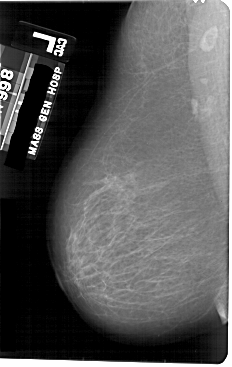

A_1816_1.LEFT_CC

LEFT_CC LINES 5491 PIXELS_PER_LINE 3376 BITS_PER_PIXEL 12 RESOLUTION 43.5 NON_OVERLAY